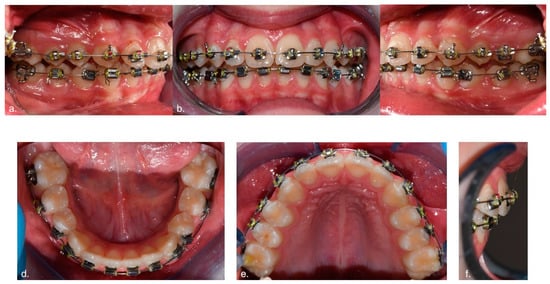

2.2. Clinical Evaluation